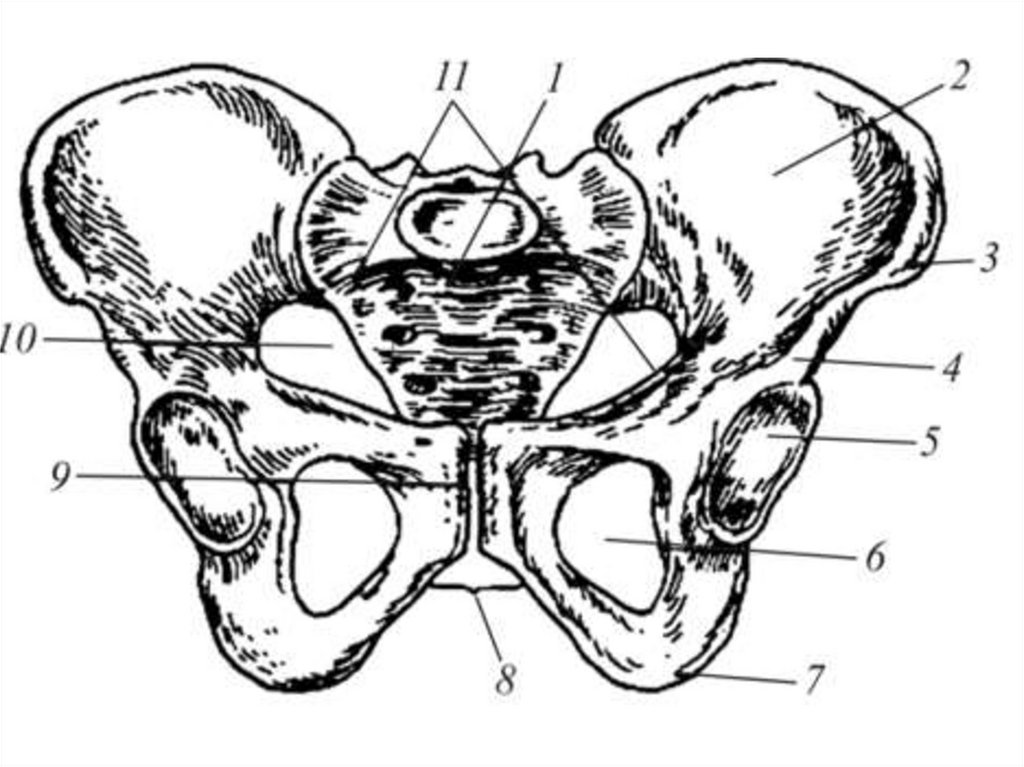

Анатомия малого таза: детальные схемы и изображения